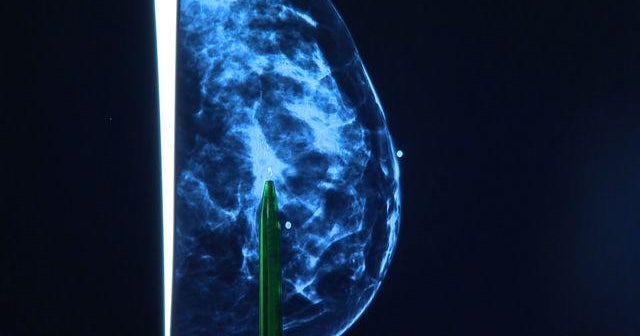

Scientists develop new classifications for breast cancer

Breast cancer researchers in Britain have come up with a new classification system for the disease which could help improve treatment. Also, a drug to fight multiple sclerosis is doing well in clinical trials. Brian Webb reports on the day's to health news.